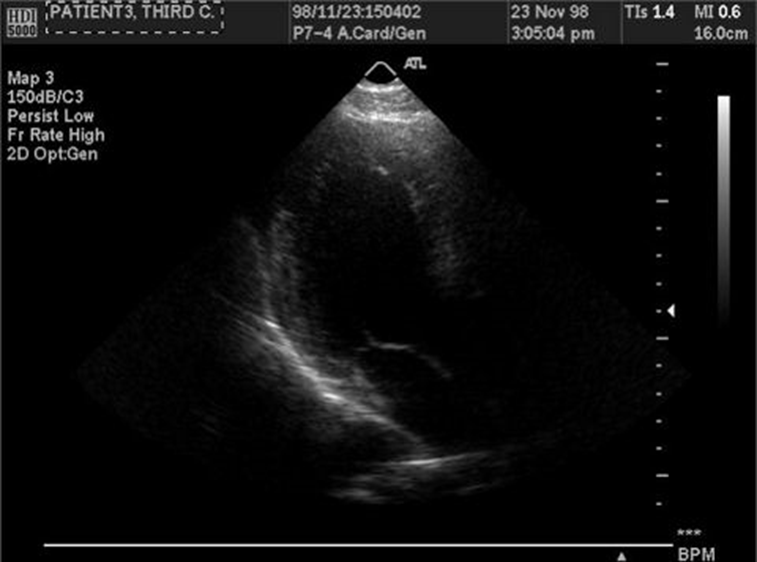

In some contexts, such as medical imaging, the content itself may not be directly identifying. A radiograph, ultrasound, or MRI scan usually does not reveal a person’s identity visually. However, metadata associated with medical images can contain disclosive information such as patient names, hospital IDs, or timestamps. The standard format for medical imaging, DICOM (Digital Imaging and Communications in Medicine), stores extensive metadata alongside the image. Therefore, medical image anonymization focuses primarily on metadata removal—deleting or replacing all patient identifiers—and, when necessary, erasing burned-in text that may appear on the image itself. Many medical imaging systems already include built-in anonymization functions for this purpose.

In the case of medical images, while it is possible to generate synthetic data, it is not always desirable. Additionally, medical images, such as X-Rays, are not really disclosive, except for any metadata shipped along the image data.

5.1.1. Medical images (DICOM)#

DICOM (Digital Imaging and Communications in Medicine) is a standard for handling, storing, printing, and transmitting information in medical imaging. It includes a file format definition and a network communications protocol. The communication protocol is an application protocol that uses TCP/IP to communicate between systems. DICOM files can be exchanged between two entities that can receive image and patient data in DICOM format.

A DICOM data object consists of several attributes, including items such as name, ID, etc., and one special attribute containing the image pixel data. One of the attributes, the modality, represents the DICOM file type. Biomagnetic imaging Bone Densitometry (X-Ray) Computed Tomography Electrocardiography Endoscopy

Other DICOM image metadata include information about the patients, which can be removed. Patient’s Name Patient ID Patient’s Birth Date Patient’s Sex Patient’s Size Patient’s Weight Patient’s Address Patient’s Mother’s Birth Name

Additionally, images might contain burned-in annotations, which must be removed.

DICOM libraries and editor software include tools to anonymize DICOM images. DICOM Library, https://www.dicomlibrary.com Sante DICOM Editor, https://www.santesoft.com/win/sante-dicom-editor/howto/anonymize.html